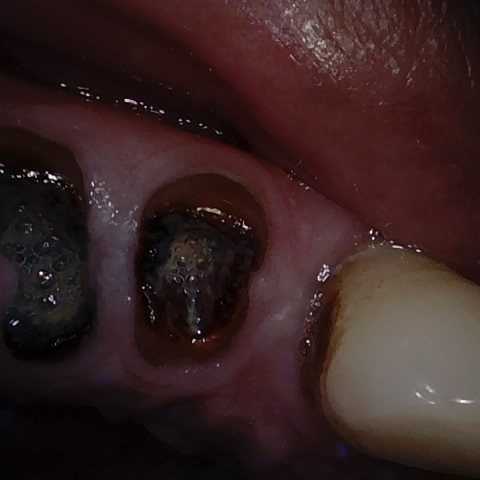

Annotated as "Good"